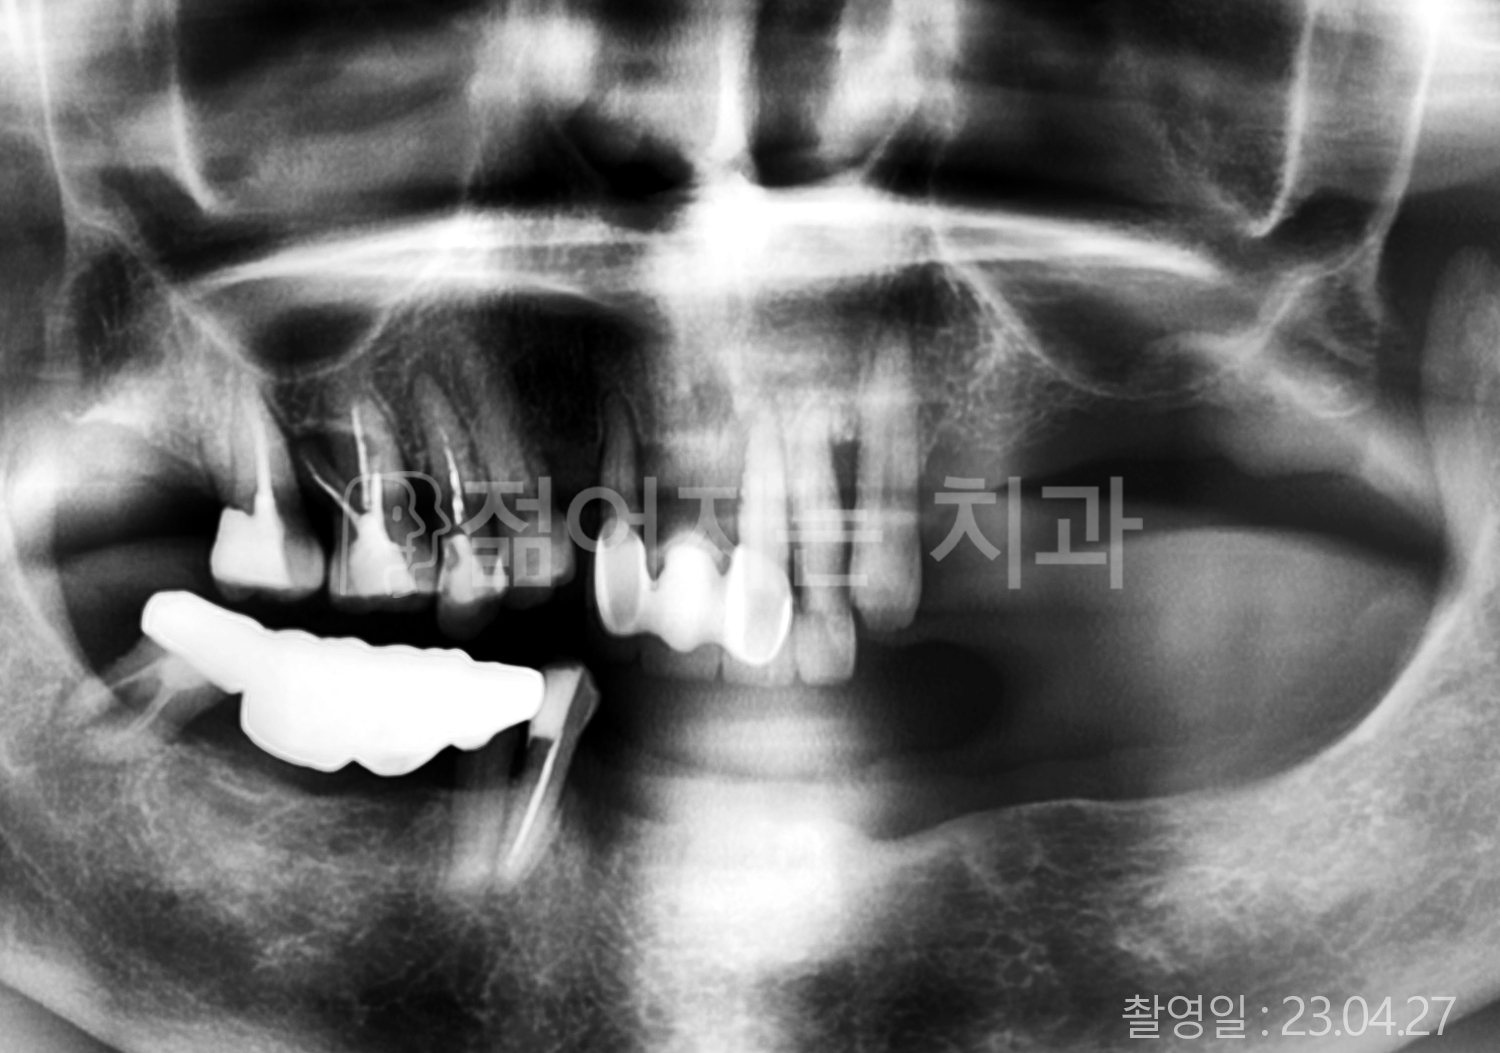

• 80대 전체치아 10개 이상 임플란트

• 60대 고혈압, 당뇨, 고지혈증 전체치아 10개 이상 임플란트

• 60대 전체치아 10개 이상 임플란트

• 60대 고혈압, 고지혈증 전체치아 10개 이상 임플란트

• 50대 고혈압, 당뇨, 고지혈증 전체치아 10개 이상 임플란트

• 70대 골다골증, 파킨스병 전체치아 10개 이상 임플란트

• 40대 전체치아 10개 이상 임플란트

• 60대 골다골증 전체치아 10개 이상 임플란트

• 40대 고혈압 전체치아 10개 이상 임플란트

• 50대 전체치아 10개 이상 임플란트

• 70대 전체치아 10개 이상 임플란트